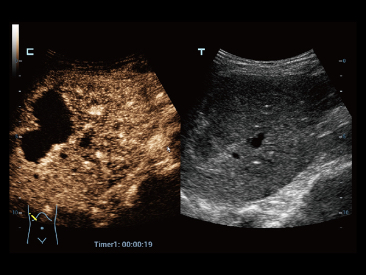

Fin dalla sua fondazione Mindray esplora continuamente nuovi modi per migliorare l'affidabilit├Ā diagnostica. Equipaggiata con la pi├╣ rivoluzionaria tecnologia ZONE Sonography?, la nuova piattaforma ZST+ di Resona 7 porta la qualit├Ā dell'immagine ecografica ad un livello superiore con l'acquisizione per zone e l'elaborazione dei dati canale.

Oltre alla qualit├Ā delle immagini di livello eccellente, Resona 7 migliora anche le capacit├Ā di ricerca clinica il rivoluzionario V Flow per la valutazione emodinamica vascolare, e l'acquisizione piani pi├╣ intelligente dal set di dati 3D per la diagnosi del sistema nervoso centrale fetale. Combinando il pi├╣ intuitivo funzionamento multi-touch basato su gesti e tutte le caratteristiche cliniche essenziali, Resona 7 sta veramente portando nuove tendenze nellŌĆÖinnovazione dellŌĆÖecografia.